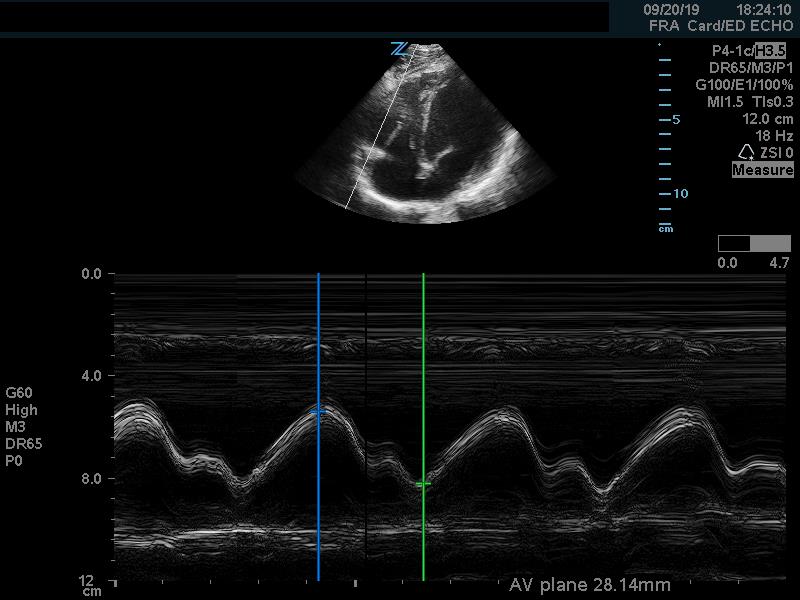

In addition to comparison of chamber size, one can further quantify RV function by using Tricuspid Annular Plane Systolic Excursion (TAPSE). This measurement indicates RV systolic function. In the apical 4 chamber view, place an M mode line through the lateral aspect of the tricuspid annulus. Measure the distance the annulus travels during the ventricular cycle. A normal TAPSE is generally 20mm or greater. (Video 5) (Figure 10) A TAPSE less than 16mm is concerning for RV strain. (Figure 11)

Figure 10. Apical 4 chamber view. M-Mode measurement of TAPSE measuring 28mm, indicating normal RV systolic function

Figure 11. Apical 4 chamber view. M-Mode measurement of TAPSE measuring 9.6mm, indicating depressed RV systolic function